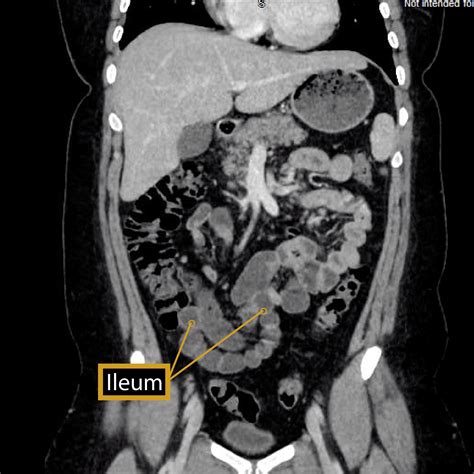

What is the Ileum?

The ileum is the final and longest segment of the small intestine. It plays a vital role in the digestive system by absorbing nutrients and water from the food we consume. The ileum is connected to the jejunum at one end and the cecum (the beginning of the large intestine) at the other. Its primary functions include:

The ileum is characterized by its thin walls and numerous folds, known as plicae circulares, which increase the surface area for absorption. It also contains Peyer's patches, which are aggregates of lymphoid tissue that play a role in the immune system by helping to protect the body from pathogens.

• CT Scans: For detailed imaging of both the ileum and ilium, providing cross-sectional views.